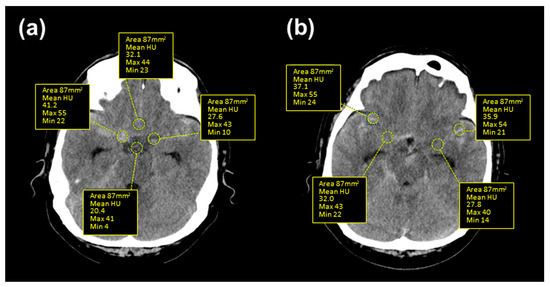

2.3. Clot Density Measurements